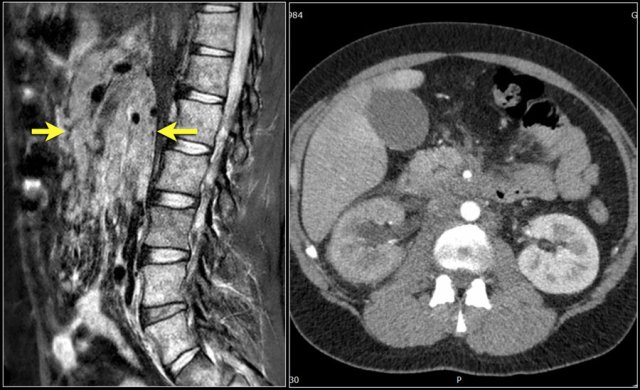

Here sagittal T1W-images demonstrating a structure of very low signal intensity at the L4L5 level (arrow) and at the L5S1 level.

Continue with the T2W-images.

T2W-images T2W-images

Also on the T2W-images the signal intensity is very low.

A CT-scan was performed to see if this could be a calcified herniated disc or some artifact.

Continue with the CT-images.

The low signal intensity could finally be explained by the vacuum phenomena due to nitrogen gas within the herniated disc both on L4L5 (red arrow) and L5S1 level (blue arrow)